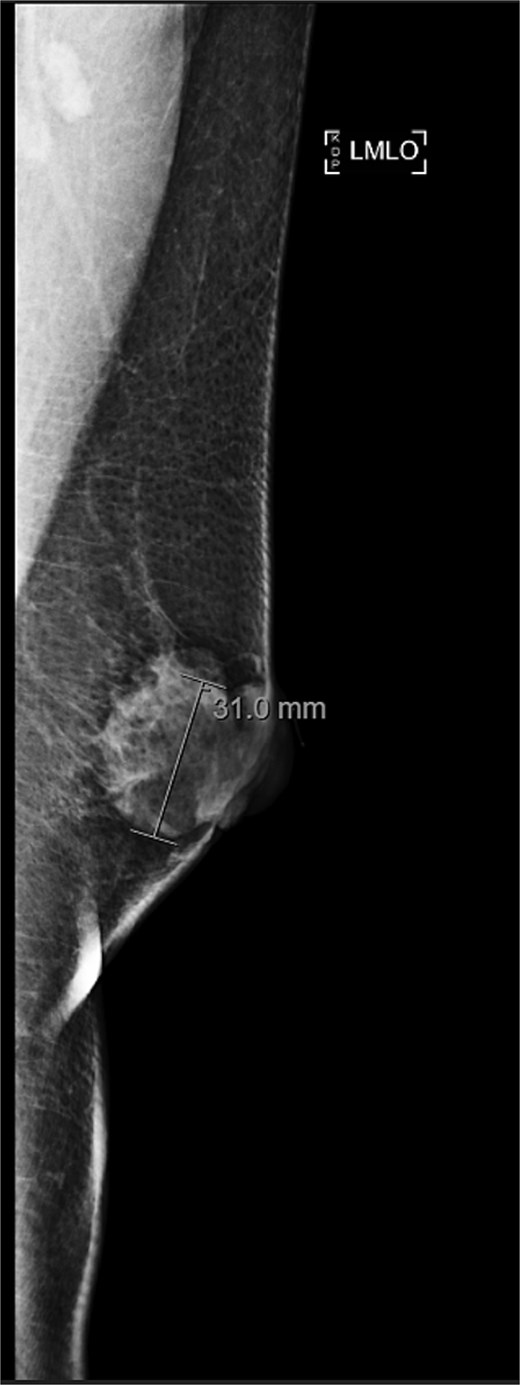

A 63-year-old male with a past medical history of heavy daily tobacco use, COPD, and a left breast leiomyoma diagnosed in 2018 presented to a general surgeon with a nonhealing left breast abscess. The patient had a persistent 3 cm retroareolar mass despite multiple incision and drainage procedures. On exam, the left axillary lymph nodes were unremarkable and the nipple, while not inverted, was chronically distorted, indurated, and inflamed. The persisting mass and inflammation were initially concerning for inflammatory breast cancer. Superficial biopsy by both a dermatologist and general surgeon were equivocal. Diagnostic mammogram and targeted left breast ultrasound revealed a retroareolar 3.3 × 3.6 × 2.7 cm heterogenous mass, corresponding to the area of palpable concern (Figs 1 and 2).

Diagnostic mammogram of left breast showing heterogenous retroareolar mass – first view.